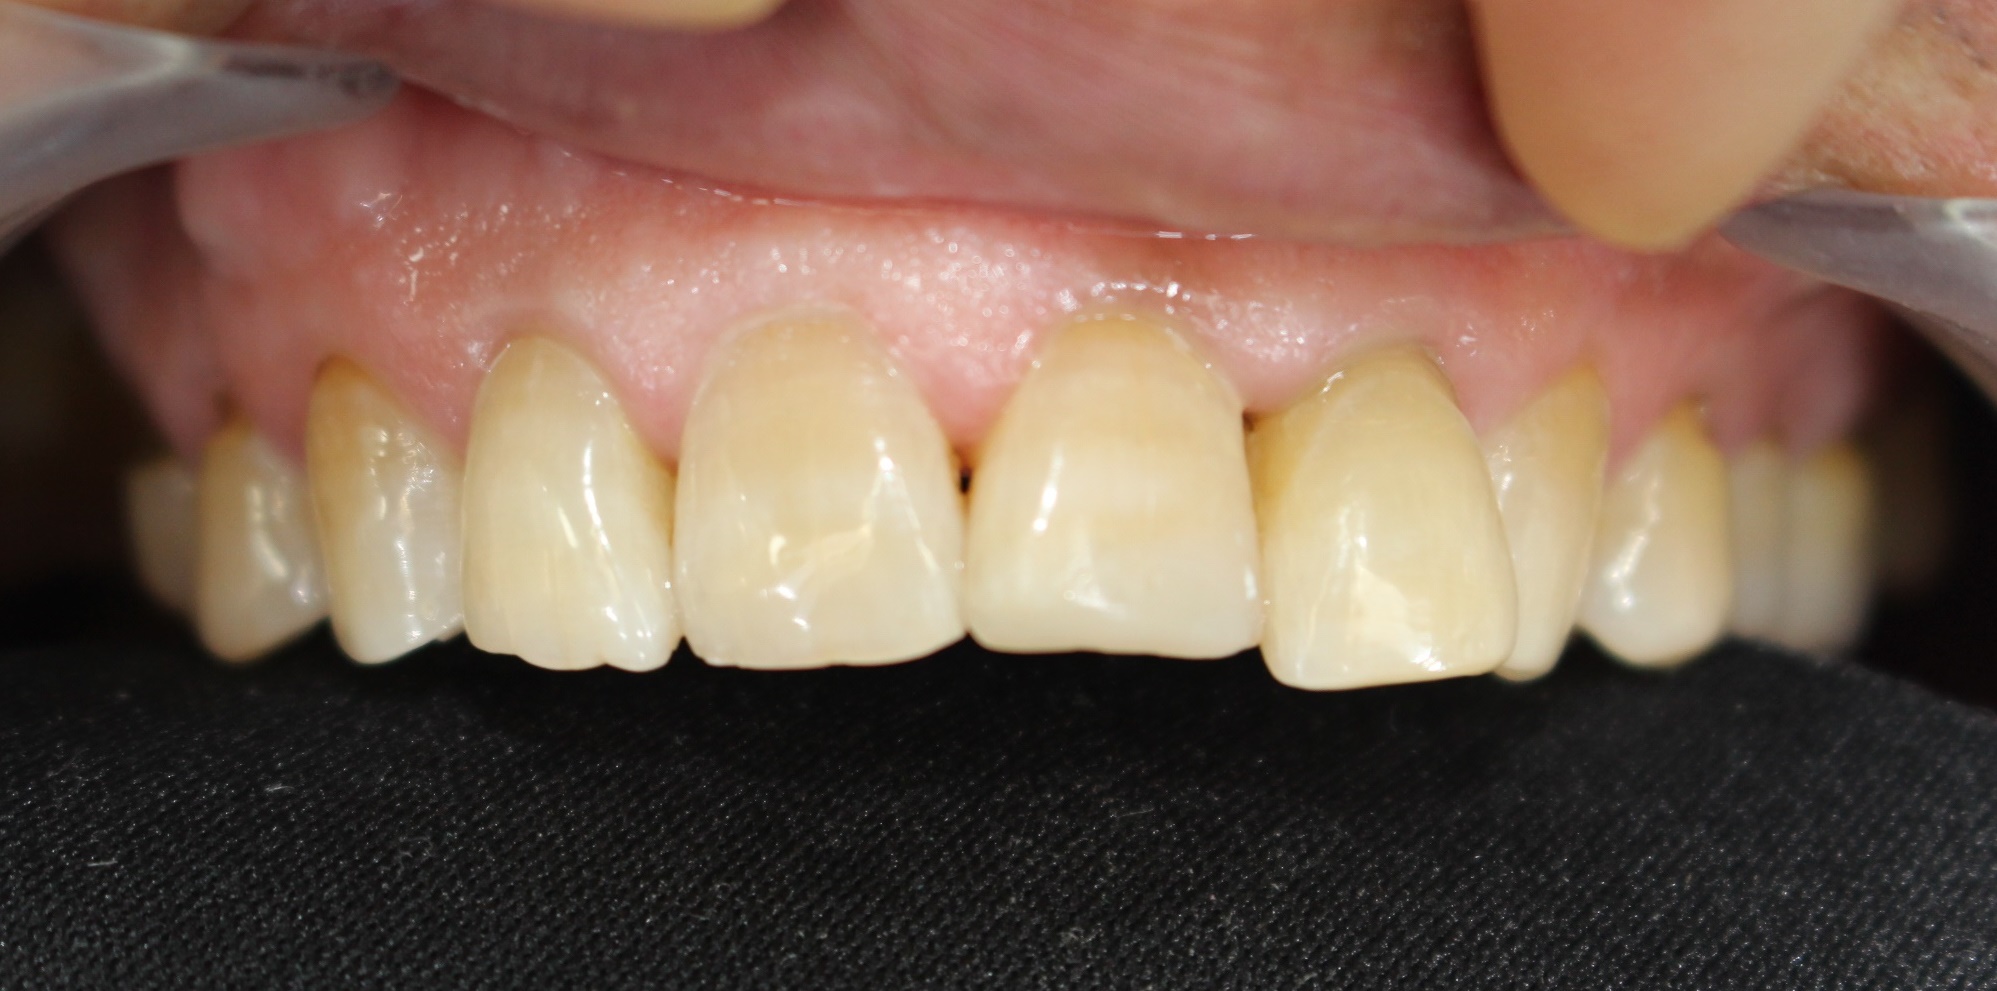

심미치료

전문가치아미백

전후사진